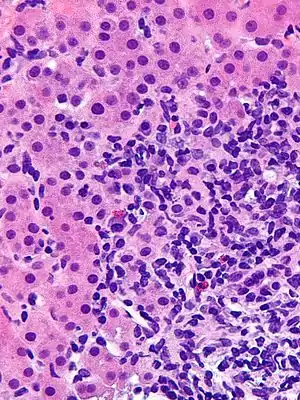

| Micrograph showing a lymphoplasmacytic interface hepatitis—the characteristic histomorphologic finding of autoimmune hepatitis. Liver biopsy. H&E stain. | |

Histological features supportive of a diagnosis of autoimmune hepatitis include:[9]

- A mixed inflammatory infiltrate centered on the portal tract

- The inflammatory infiltrate may breach the interface between the portal tract and liver parenchyma: so-called interface hepatitis

- The most numerous cell in the infiltrate is the CD4-positive T cell.

- Plasma cells may be present within the infiltrate. These are predominantly IgG-secreting.

- Eosinophils may be present within the infiltrate.

- Emperipolesis, where there is penetration of one cell through another, within the inflammatory infiltrate

- Varying degrees of necrosis of periportal hepatocytes.

- In more severe cases, necrosis may become confluent with necrotic bridges forming between central veins.

- Hepatocyte apoptosis manifest as acidophils or apoptotic bodies.

- Rosettes of regenerating hepatocytes.

- Any degree of fibrosis from none to advanced cirrhosis

- Biliary inflammation without destruction of biliary epithelial cells in a minority of cases.